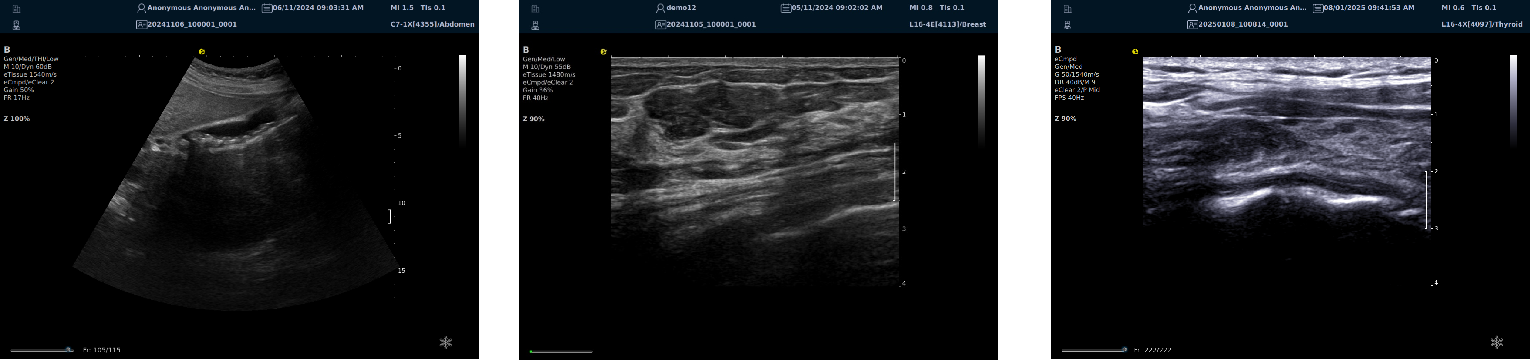

优异的二维图像

image.png